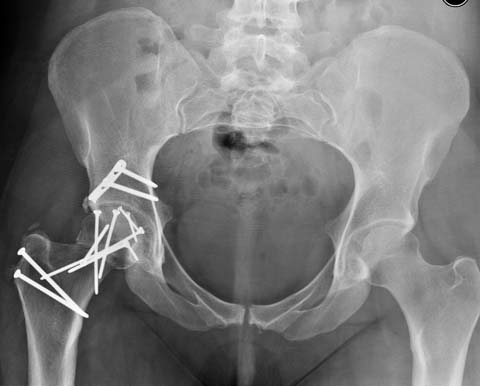

Здесь выбрана правильная тактика и операция сделано на хорошо. Надеюсь, промах с фиксацией не создаст проблему. Можно было добавить в задную стенку spring plate и винты до медиального кортекса в фиксации вертела.

Здесь клинические примеры: Первый случай передний доступ, второй с ICP monitor Flipp Trochanteris

и с переломом заднего края.